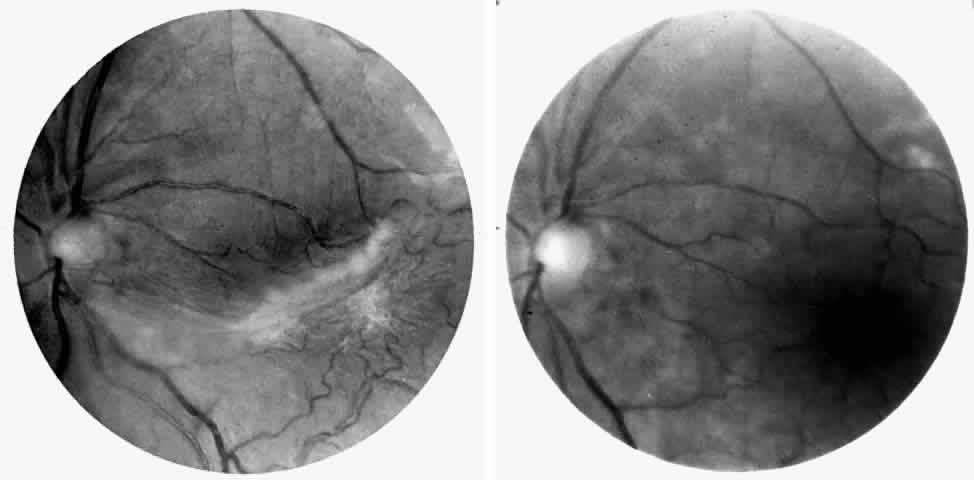

Retinal Artery Occlusions

Occlusions of the central retinal artery and major arteriolar branches are probably most frequent in young patients with homozygous sickle cell anemia; however, they may also occur with other sickling genotypes (Fig. 7).39,83,84 They may cause permanent or transient visual loss and can occur simultaneously in both eyes.85–87 Arterial occlusion has also been reported to occur as a complication of retrobulbar anesthesia and following compression of the eye during photocoagulation (Fig. 8).88

Retinal artery occlusion has also been reported in patients with sickle cell trait secondary to airplane travel,70 with elevated intraocular pressure following blunt trauma,53,54 with extreme dehydration,89 and in association with tuberculosis and systemic lupus erythematosus.90